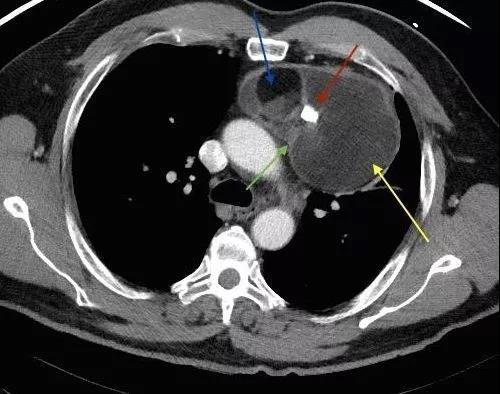

做完全腹CT檢查后,她被告知腹腔有一大包塊。這個包塊存于腹膜后,經(jīng)過多年吸附腹主動脈營養(yǎng)已長至10多公分,且將胰腺和脾臟擠至胸腔邊緣。最有意思的是,這個包塊竟有頭發(fā)、骨骼等組織,極像畸形的胎兒。

"手術(shù)過程也比較復(fù)雜,一是要完整地將包塊從腹主動脈上剝離,同時避免傷害到人體大動脈——腹主動脈;二是由于包塊與脾臟、胰腺粘連嚴重,必須在切除包塊時不能誤傷這兩個器官?!眳⑴c手術(shù)的主任醫(yī)師高文燦說。